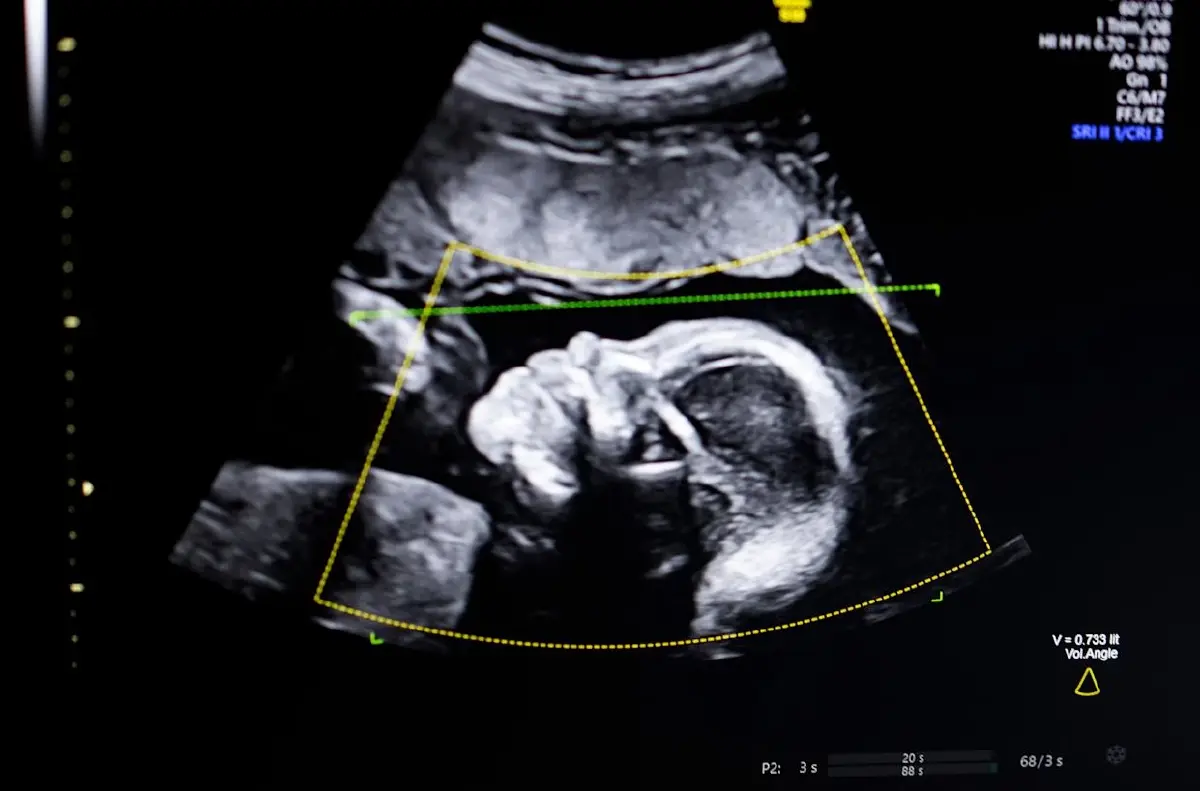

โดยเทคโนโลยีดังกล่าวถูกออกแบบมาเพื่อช่วยแพทย์ตรวจจับความผิดปกติของทารกในครรภ์ผ่านภาพอัลตราซาวด์ได้อย่างแม่นยำยิ่งขึ้น

BioticsAI นำเทคโนโลยี Computer Vision AI เข้ามาประยุกต์ใช้ในการประเมินคุณภาพของภาพอัลตราซาวด์ ตรวจสอบความครบถ้วนสมบูรณ์ทางกายวิภาคของทารก และจัดทำรายงานผลตรวจแบบอัตโนมัติ

BioticsAI ชี้ให้เห็นว่า แม้การอัลตราซาวด์จะเป็น "หัวใจสำคัญ" ของการติดตามการตั้งครรภ์ แต่คุณภาพของภาพถ่ายที่ต่ำมักนำไปสู่การวินิจฉัยที่คลาดเคลื่อน